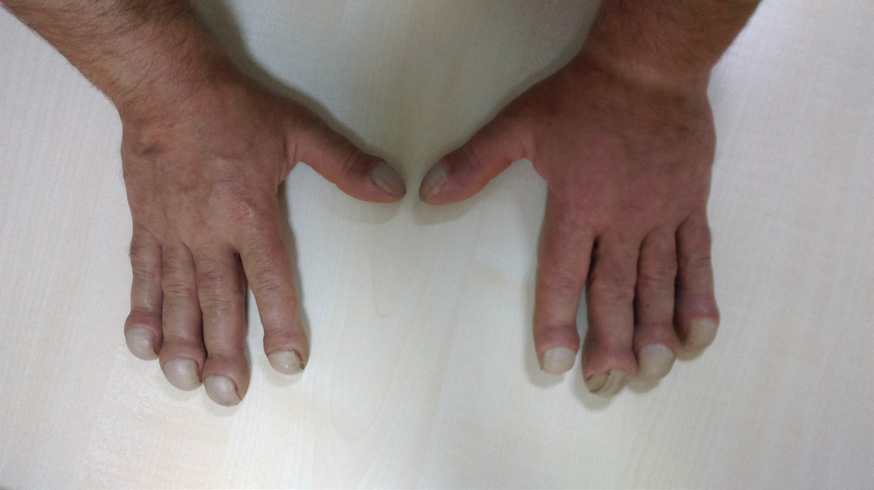

A 26-year-old male presented to the outpatient clinic because of expansion of his hands and feet since the age of 12 (Figure 1). With widespread pain and swelling in both ankles and knees. Expansion of his hands was insidious in onset and associated with excessive sweating. Positive family history of same complaint in milder degree in his father and elder sister. He had another healthy sister and brother. There was a kinship between the patient's parents. In physical examination, there was severe clubbing of all fingers and toes with enlarged distal extremities. The skin of both hands and feet was thickened. He had arthritis in both knees and ankles. X-ray images showed hypertrophic osteoarthropathy and acroosteolysis (Figure 2). We confirmed the synovitis by magnetic resonance imaging of the knee. Complete blood count, serum glucose, alkaline phosphatase, calcium and phosphorous were normal. Serum growth hormone (GH), insulin-like growth factor 1 (IGF1), thyroid stimulating hormone, free thyroxine 4, prolactin, testosterone, adrenocorticotrophic hormone, and cortisol were normal. Sedimentation rate (ESR) and C - reactive protein were found to be high (104mm/h, 21mg/L, respectively). The patient was diagnosed as pachydermoperiostosis after exclusion of excessive GH production. Treatment including colchicine, acemetacin, and biphosphonate was initiated. Arthritis was improved dramatically, and remarkably patient's symptoms were calm down in a short period.

Figure 1 26 years old patient expansion of hands and feet since the age of 12.